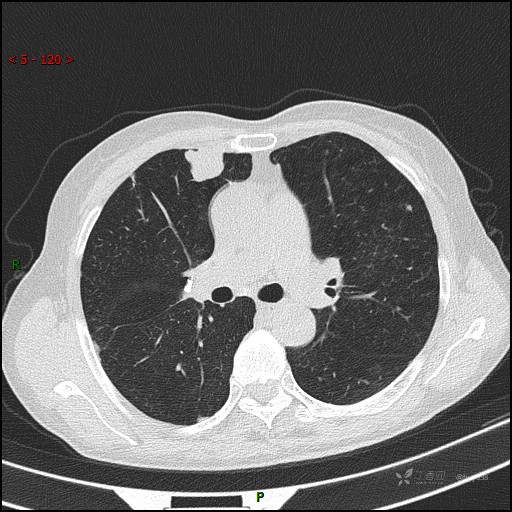

辅助检查:CT

讨论:病变性质?

胸部CT平扫

增强动脉期